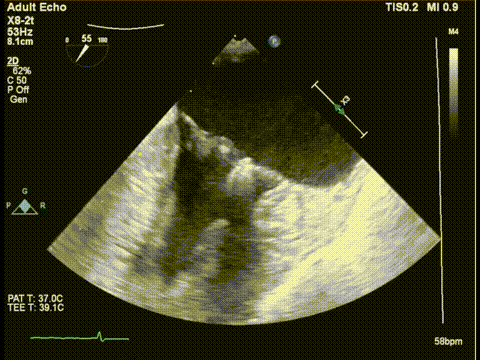

三尖瓣胃底界面

三尖瓣胃底界面color

调整胃底界面评估三尖瓣夹子位置